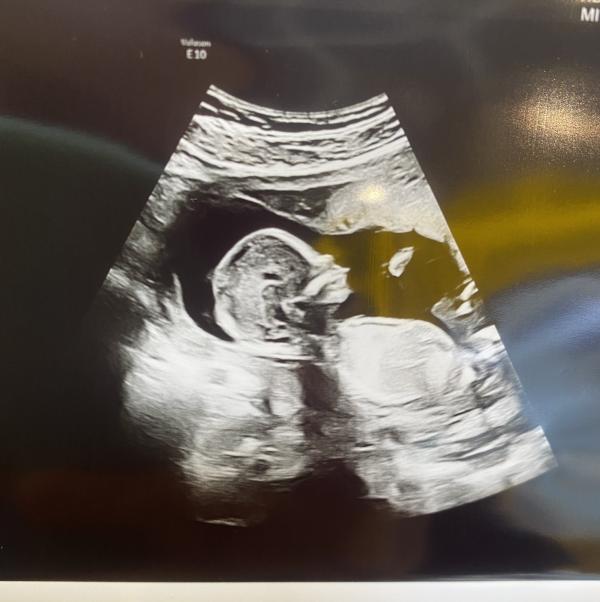

Для успокоения , сходила на узи 😅

Малышку- девочку подтвердили 👸🏽 138 грамм🥰

Всё хорошо , прикрепление по передней стенке

Срок 15 нед 2дня ✨